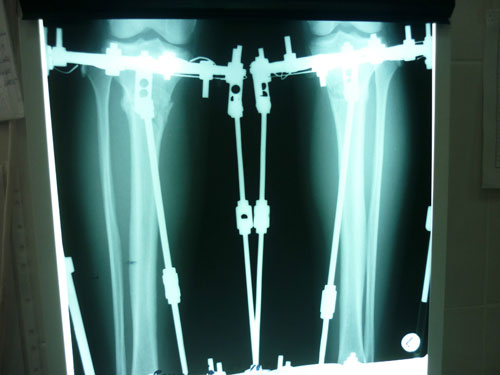

Также высылаю снимки, сделала рентген свежий срок 3 мес, вот такое получилось качество,левая боковая не очень видна((.

Посмотрите действит-но ли можно снимать,или еще походить, мне как неспециалисту непонятно((( Я смотрела снимок Бакты перед снятием- там тоже есть черные места,но тем не менее мозоль хорошая.

Здравствуйте,Bella! У Вас всё срослось - пере срослось. Давно пора снимать аппараты. Приезжайте.